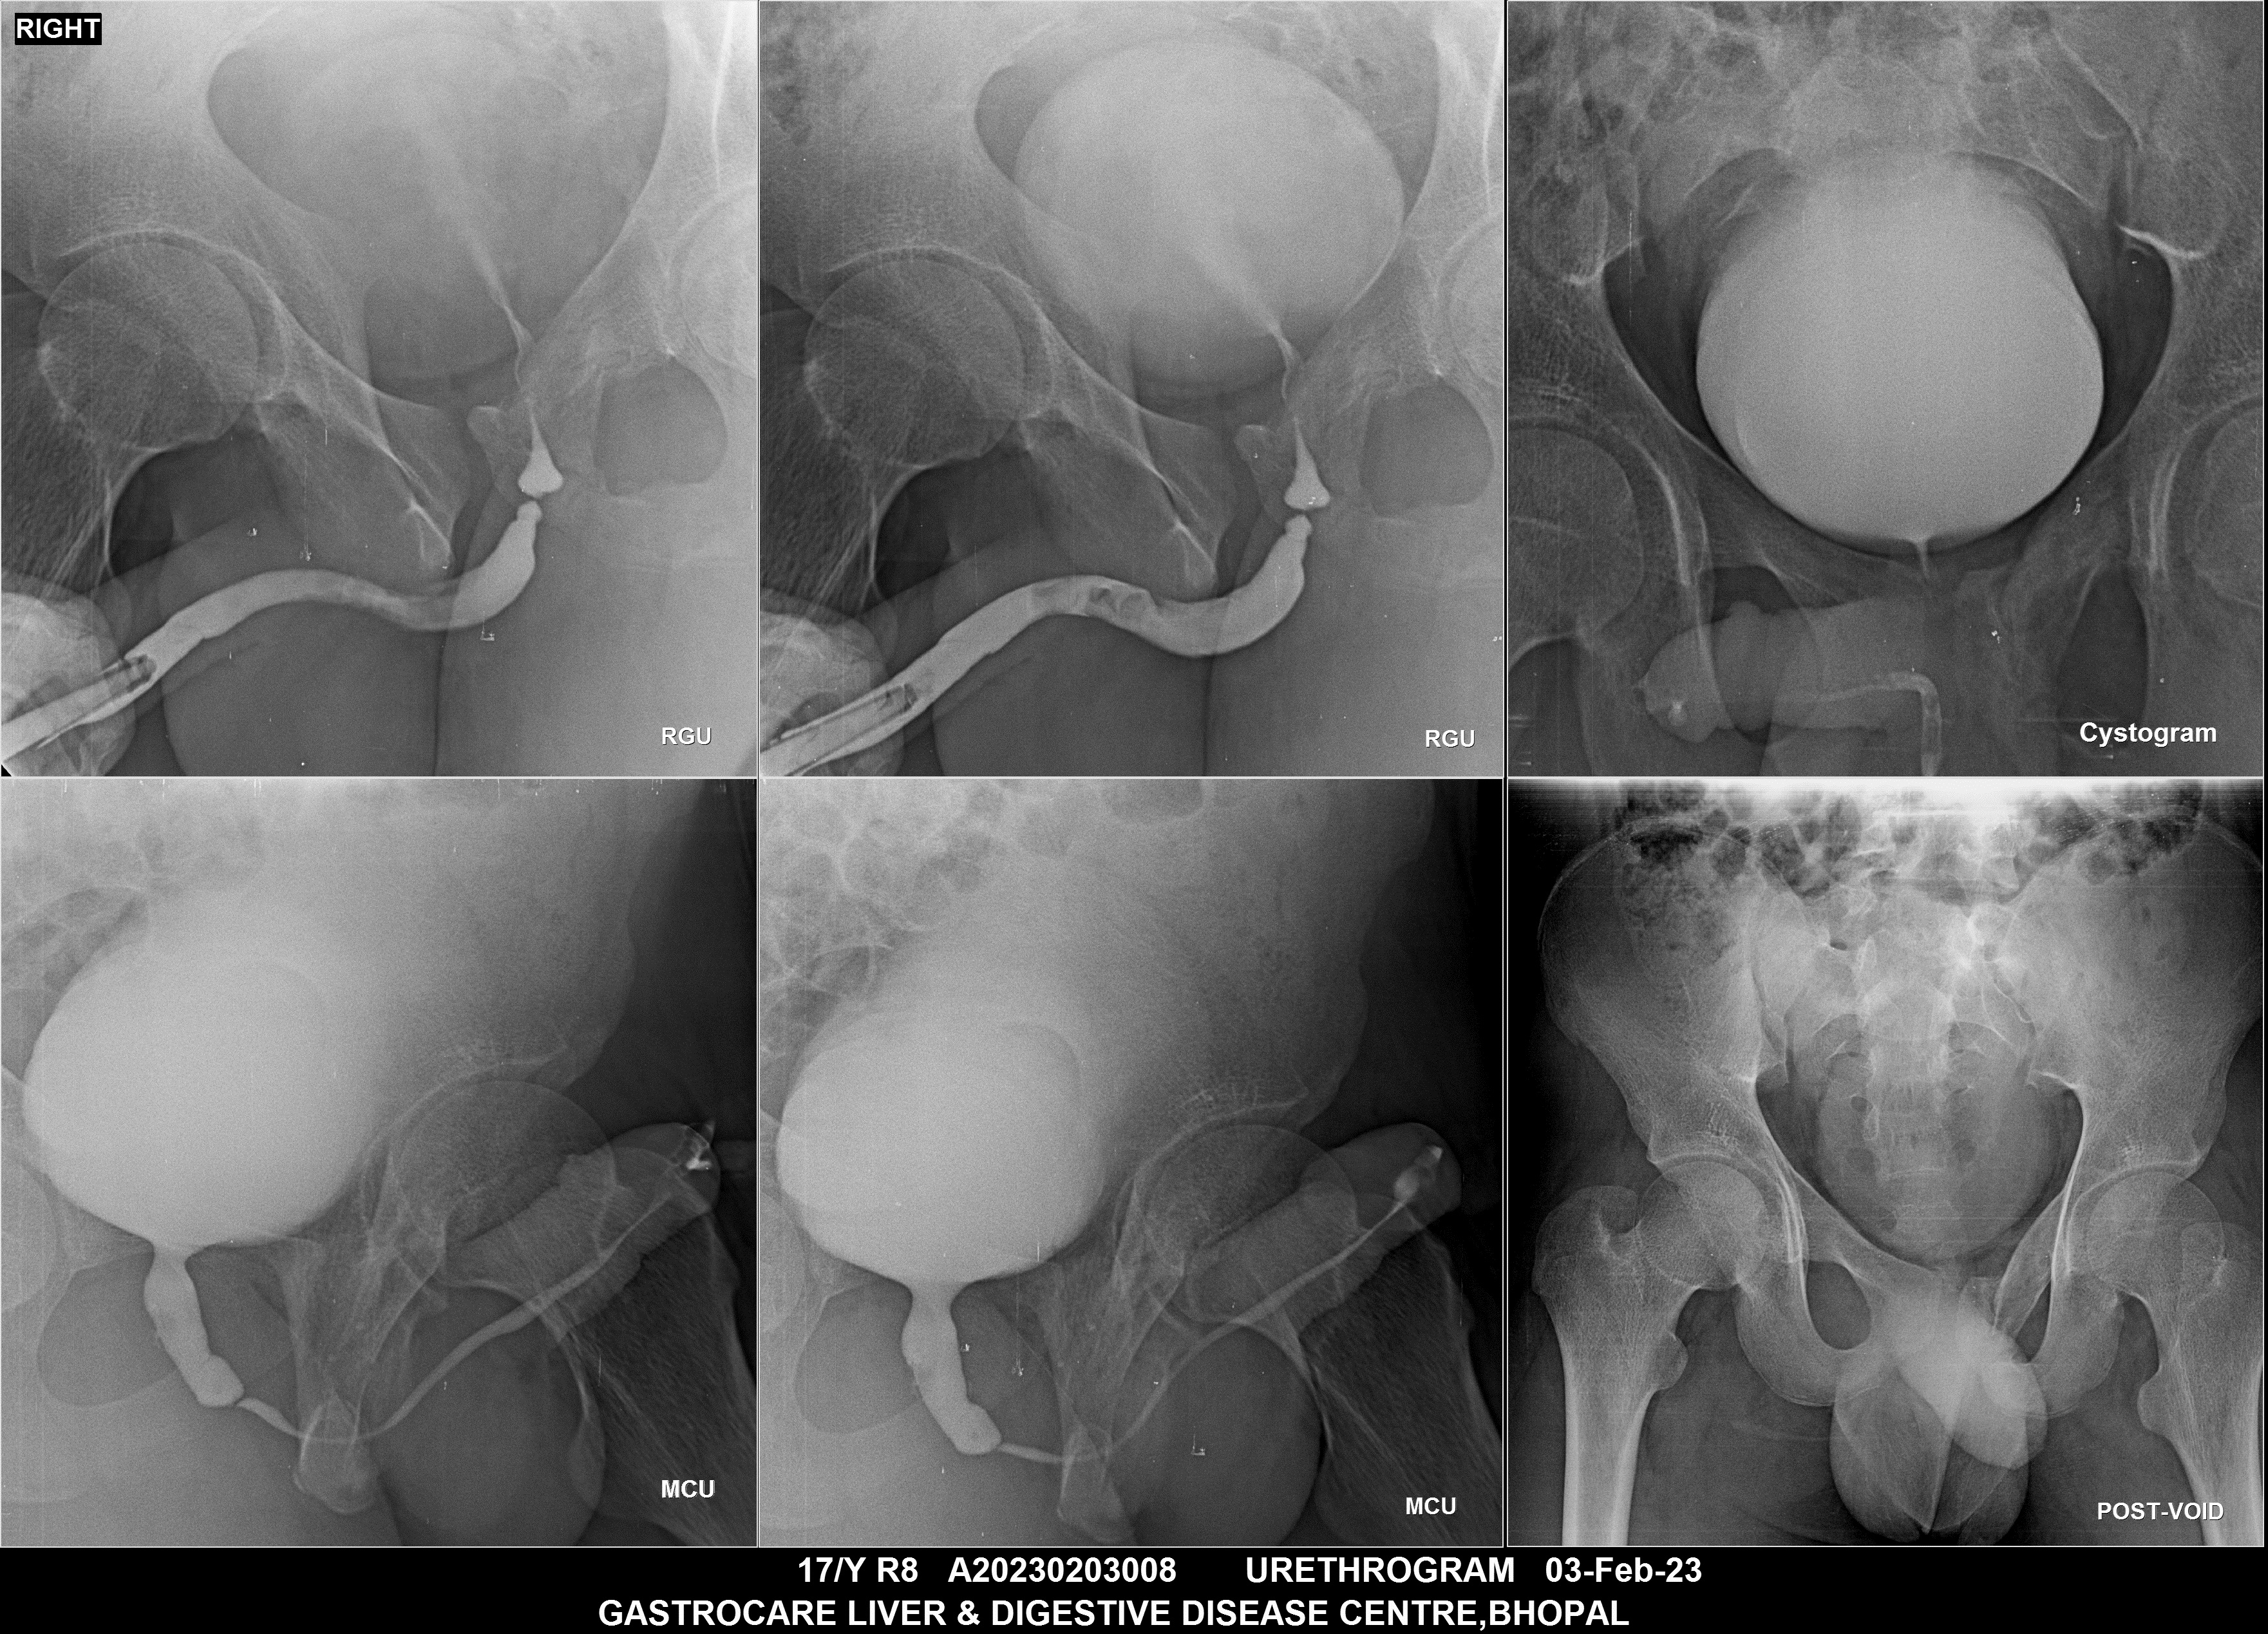

Section: URETHROGRAM Total: 95 images